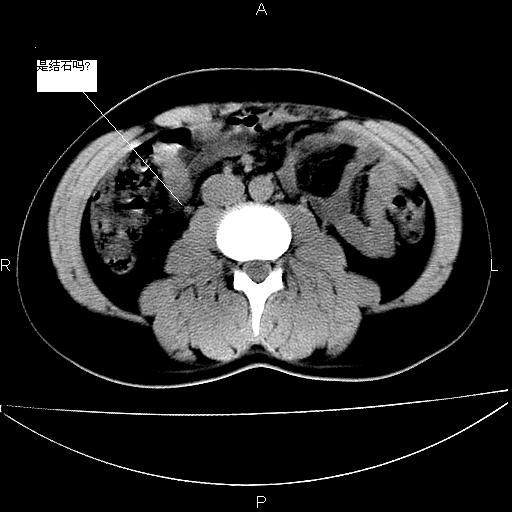

男 25岁 自述 尿频尿急,排尿困难20多天.无腰痛, b超说左肾盂轻度积水,左输尿管上端扩张.未见结石影. ct我看双侧肾盂轻度积水,双输尿管上端都扩张,大家看看能看见结石吗?

箭头所指不是输尿管,壶腹型肾盂。

肾外肾盂,必要时+c